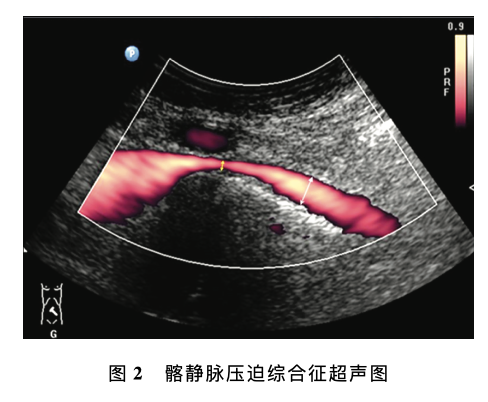

腹部及外周静脉血管超声若干临床常见问题专家共识

意见一:下肢静脉反流超声检查的推荐体位推荐体位为头高脚低位 (建议使用电动检查床), 即检查床头侧高于足侧,与地面夹角约30。条件有限的情况下可选择站立位或坐位,不推荐俯卧位评价下肢静脉反流。意见二:Valsalva (乏氏动作)的适用性乏氏动作主要用于评估隐-股静脉瓣、股静脉近 端静脉瓣的功能,不适于下肢远端静脉反流......